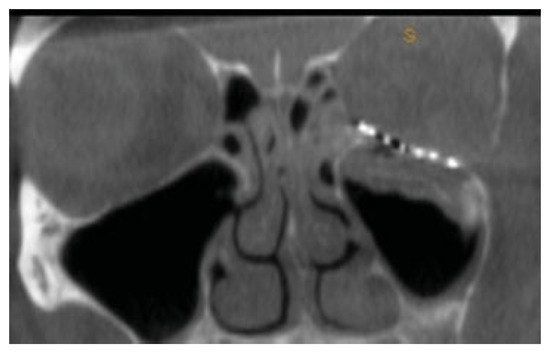

Figure 4.

Intra-operative coronal CT scan of posterior ledge and precise relationship to the titanium implant.

Figure 5.

Coronal view with correct adaptation of the plate at medial aspect of the inferior orbital fissure.

Figure 6.

Intraoperative coronal computed tomographic imaging of orbital plate from Case 1.